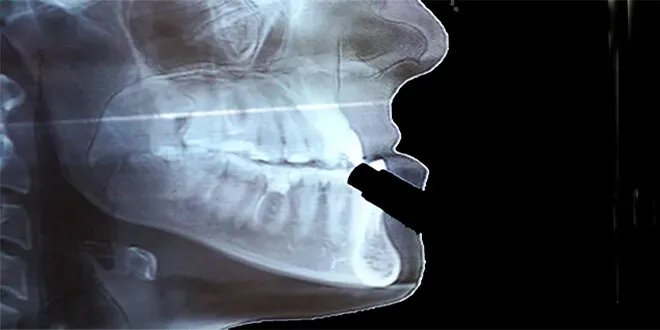

طوكيو-سانا كشف فريق بحثي من جامعة كيوتو اليابانية عن إنجاز علمي هام يتمثل في تطوير عضيات (نُظم عضوية مصغرة) تحاكي تكوُّن عظم الفك البشري، وذلك باستخدام الخلايا الجذعية.

وبحسب الدراسة التي نُشرت نتائجها في المجلة الدولية للعلوم "Nature Biomedical Engineering"، تمكن الباحثون بقيادة الأستاذين المساعدين سوتا موتويكي وإيكيا ماكوتو من قسم البحوث السريرية التطبيقية بجامعة كيوتو، من تصنيع هذه العضيات. اعتمد الباحثون في ذلك على خطوات تبدأ من الخلايا العرفية العصبية البشرية المشتقة من الخلايا الجذعية، وصولاً إلى الخلايا الأديمية الظاهرة المتوسطة، لإنتاج بنية ثلاثية الأبعاد مطابقة لعظم الفك.